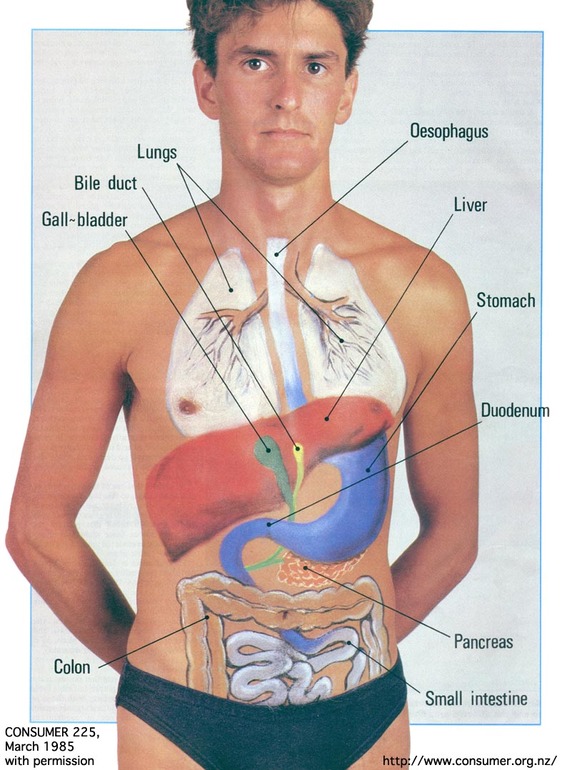

Раздел: Фотопанорама